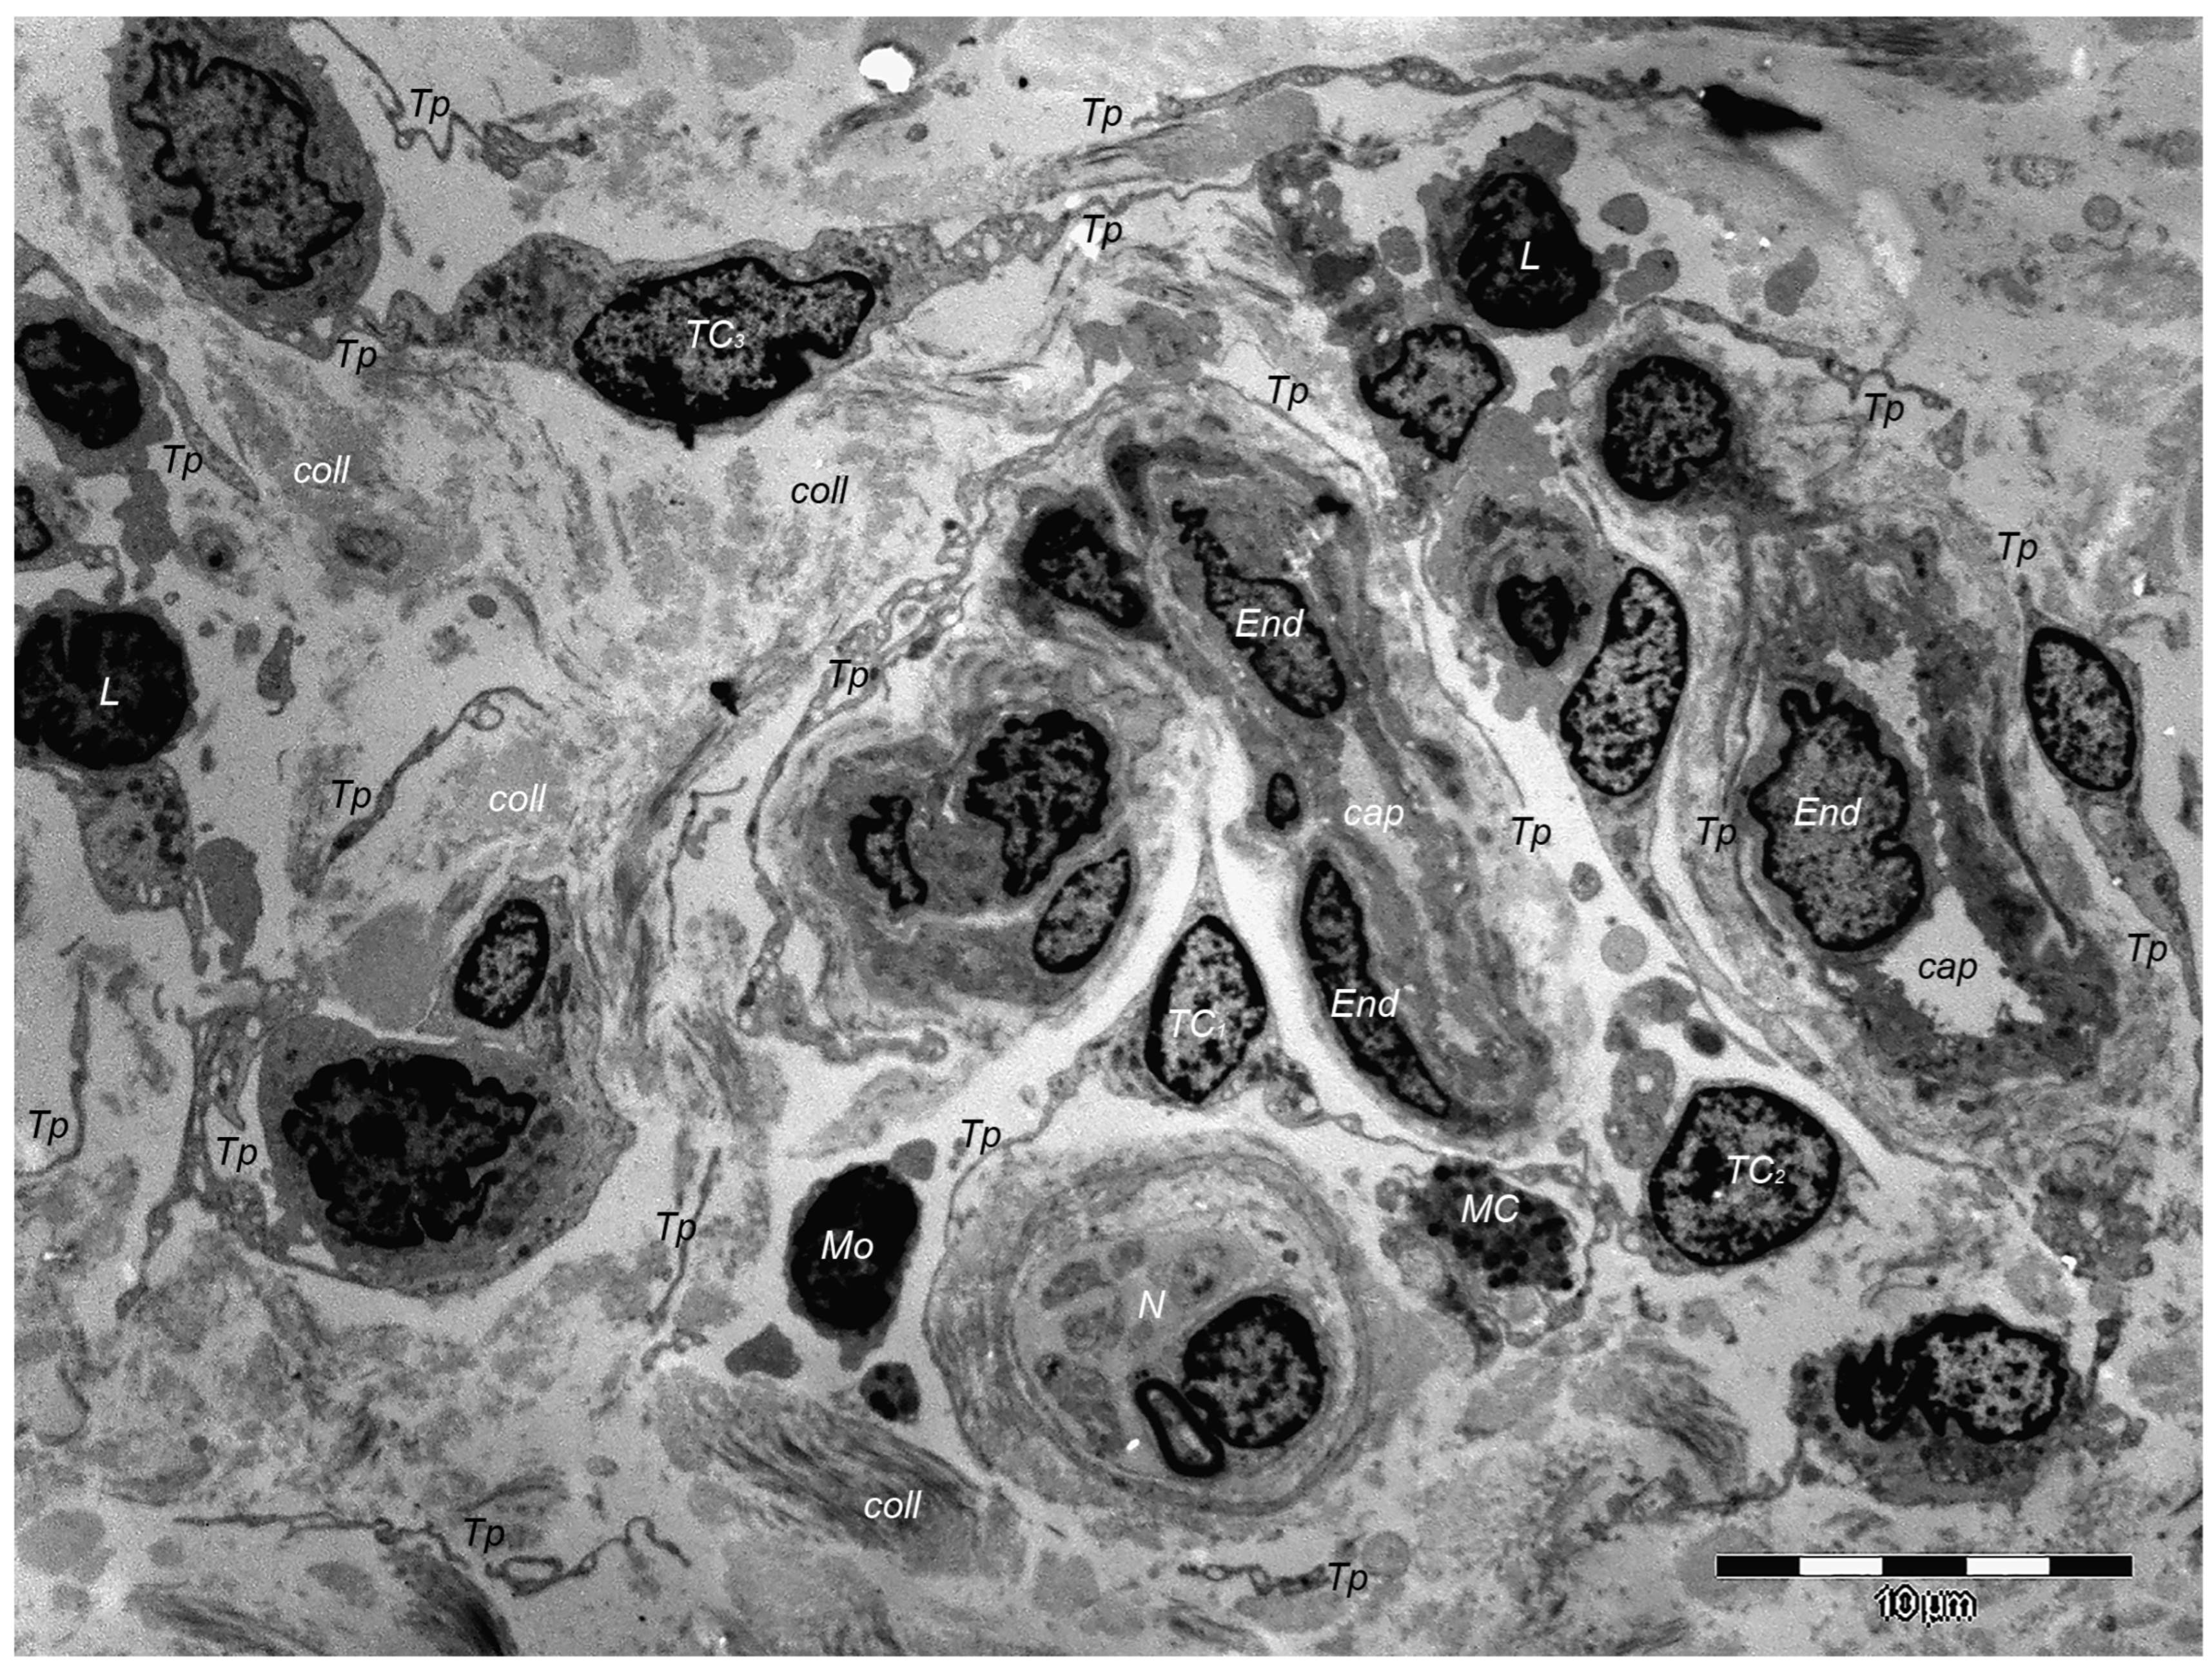

9. Dermal TCs: A Distinct Cell Population with a Promising Skin Regenerative Potential

- Rusu, M.C.; Mirancea, N.; Mănoiu, V.S.; Vâlcu, M.; Nicolescu, M.I.; Păduraru, D. Skin Telocytes. Ann. Anat.—Anat. Anz. 2012, 194, 359–367. [Google Scholar] [CrossRef] [PubMed]

- Manole, C.G.; Soare, C.; Ceafalan, L.C.; Voiculescu, V.M. Platelet-Rich Plasma in Dermatology: New Insights on the Cellular Mechanism of Skin Repair and Regeneration. Life 2023, 14, 40. [Google Scholar] [CrossRef] [PubMed]

- Wang, L.; Xiao, L.; Zhang, R.; Jin, H.; Shi, H. Ultrastructural and Immunohistochemical Characteristics of Telocytes in Human Scalp Tissue. Sci. Rep. 2020, 10, 1693. [Google Scholar] [CrossRef] [PubMed]

- Díaz-Flores, L.; Gutiérrez, R.; Pino García, M.; González, M.; Díaz-Flores, L.; Francisco Madrid, J. Telocytes as a Source of Progenitor Cells in Regeneration and Repair through Granulation Tissue. Curr. Stem Cell Res. Ther. 2016, 11, 395–403. [Google Scholar] [CrossRef]

- Díaz-Flores, L.; Gutiérrez, R.; García, M.P.; González-Gómez, M.; Rodríguez-Rodriguez, R.; Hernández-León, N.; Díaz-Flores, L.; Carrasco, J.L. Cd34+ Stromal Cells/Telocytes in Normal and Pathological Skin. Int. J. Mol. Sci. 2021, 22, 7342. [Google Scholar] [CrossRef] [PubMed]